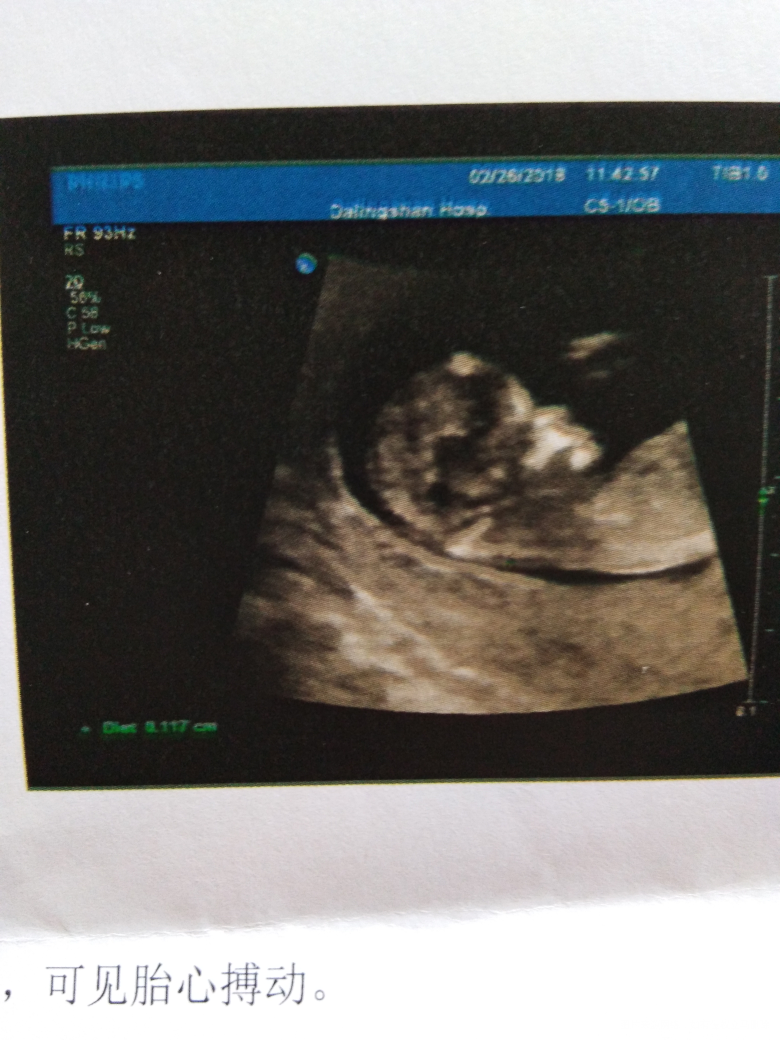

今天上午检查的结果!请帮忙看下